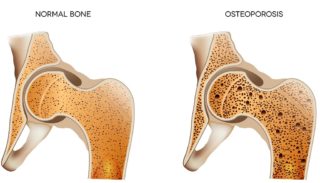

Being active is also essential for your overall health and wellbeing. It helps keep your muscles, bones and joints strong so that you can keep moving. It reduces your risk of developing other conditions such as heart disease, osteoporosis, and diabetes. It boosts your mood, benefits your mental health, helps with weight control and improves sleep.